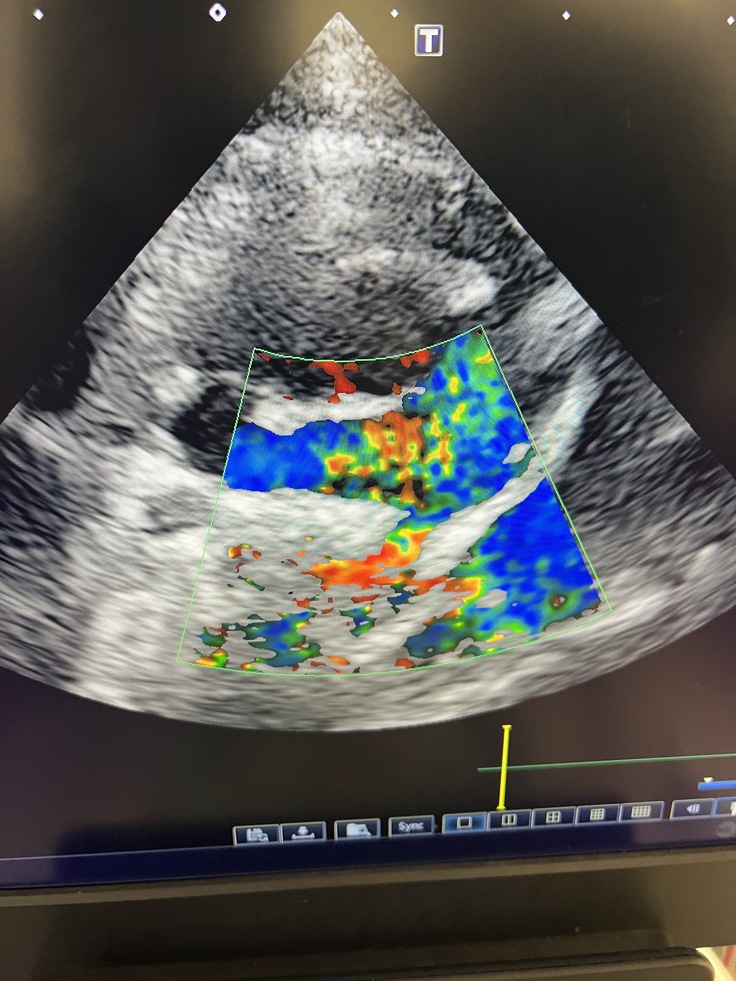

↑つる子のエコー

エコー検査では肺動脈に通常では赤色と青色は見られても良いのですが、この子は出てはいけない色(黄色や緑色)が見られ明らかに異常な状態です。